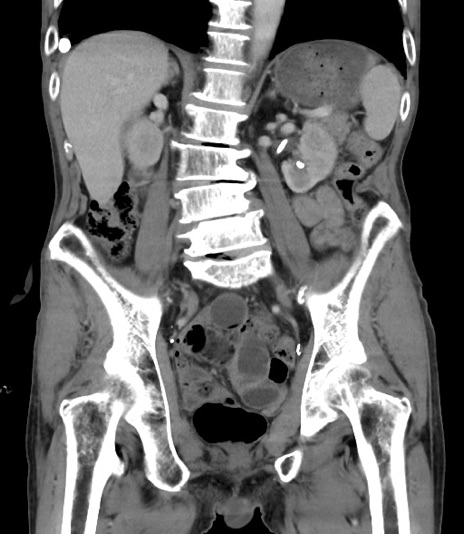

症例3(冠状断像)

【症例】 70歳代男性

【主訴】右鼠径部腫瘤、疼痛

【現病歴】本日朝より上記主訴あり、受診。

【既往歴】膀胱癌にて膀胱全摘、両側尿管皮膚瘻

【データ】WBC 5600、CRP 0.56